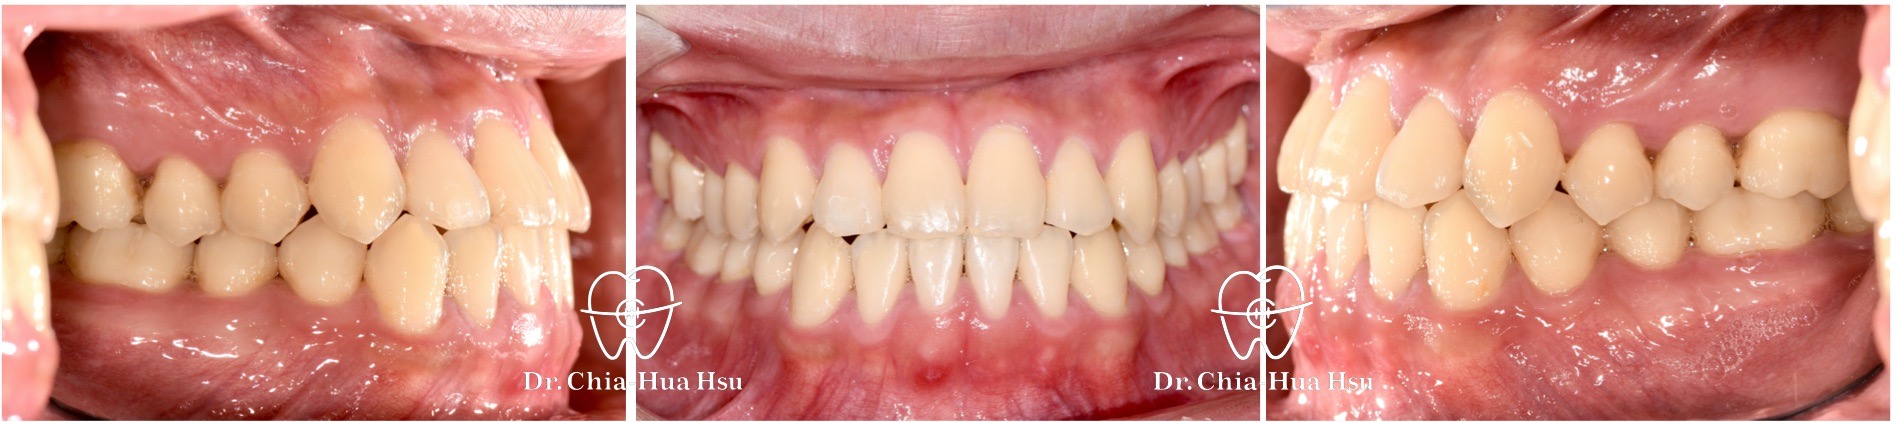

• 病患主訴:前牙錯咬、不整齊,有戽斗臉型,但不想做正顎手術。

• 問題分析:患者是輕微的骨骼三類咬合(Skeletal Class III)、下巴過長(戽斗)、前牙錯咬以及齒列不整齊。

• 治療方式:使用傳統金屬矯正器,並搭配垂直向橡皮筋牽引(Vertical elastics)使牙齒萌出。

• 治療時間:2 年。

• 治療結果:門牙露出增加、齒列排齊 ; 下臉部高度微增使下巴順時針微量旋轉,以修飾戽斗臉型。

治療前

治療後